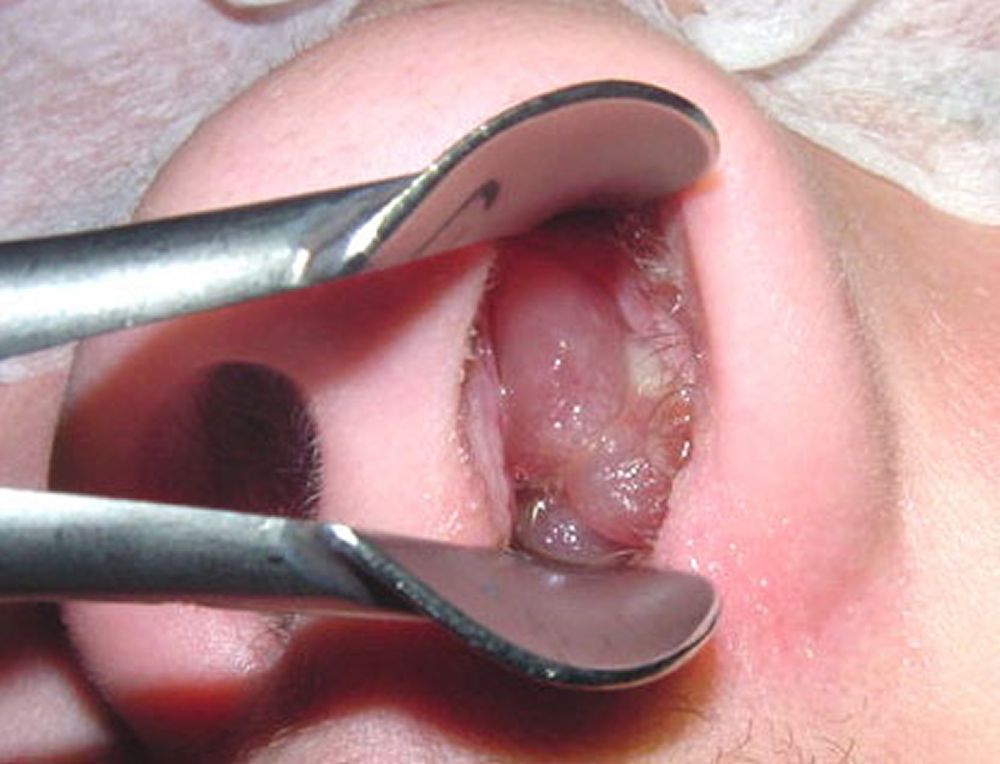

鼻茸スレ

鼻から取り出す瞬間が気持ちいい

でかすぎる場合は口から取り出す

>この肉片はなに?

鼻の中に出来たポリープだよ

鼻茸と呼ぶ

台湾のお医者さん

鼻にピンセット入れて直接引っ張り出す力業